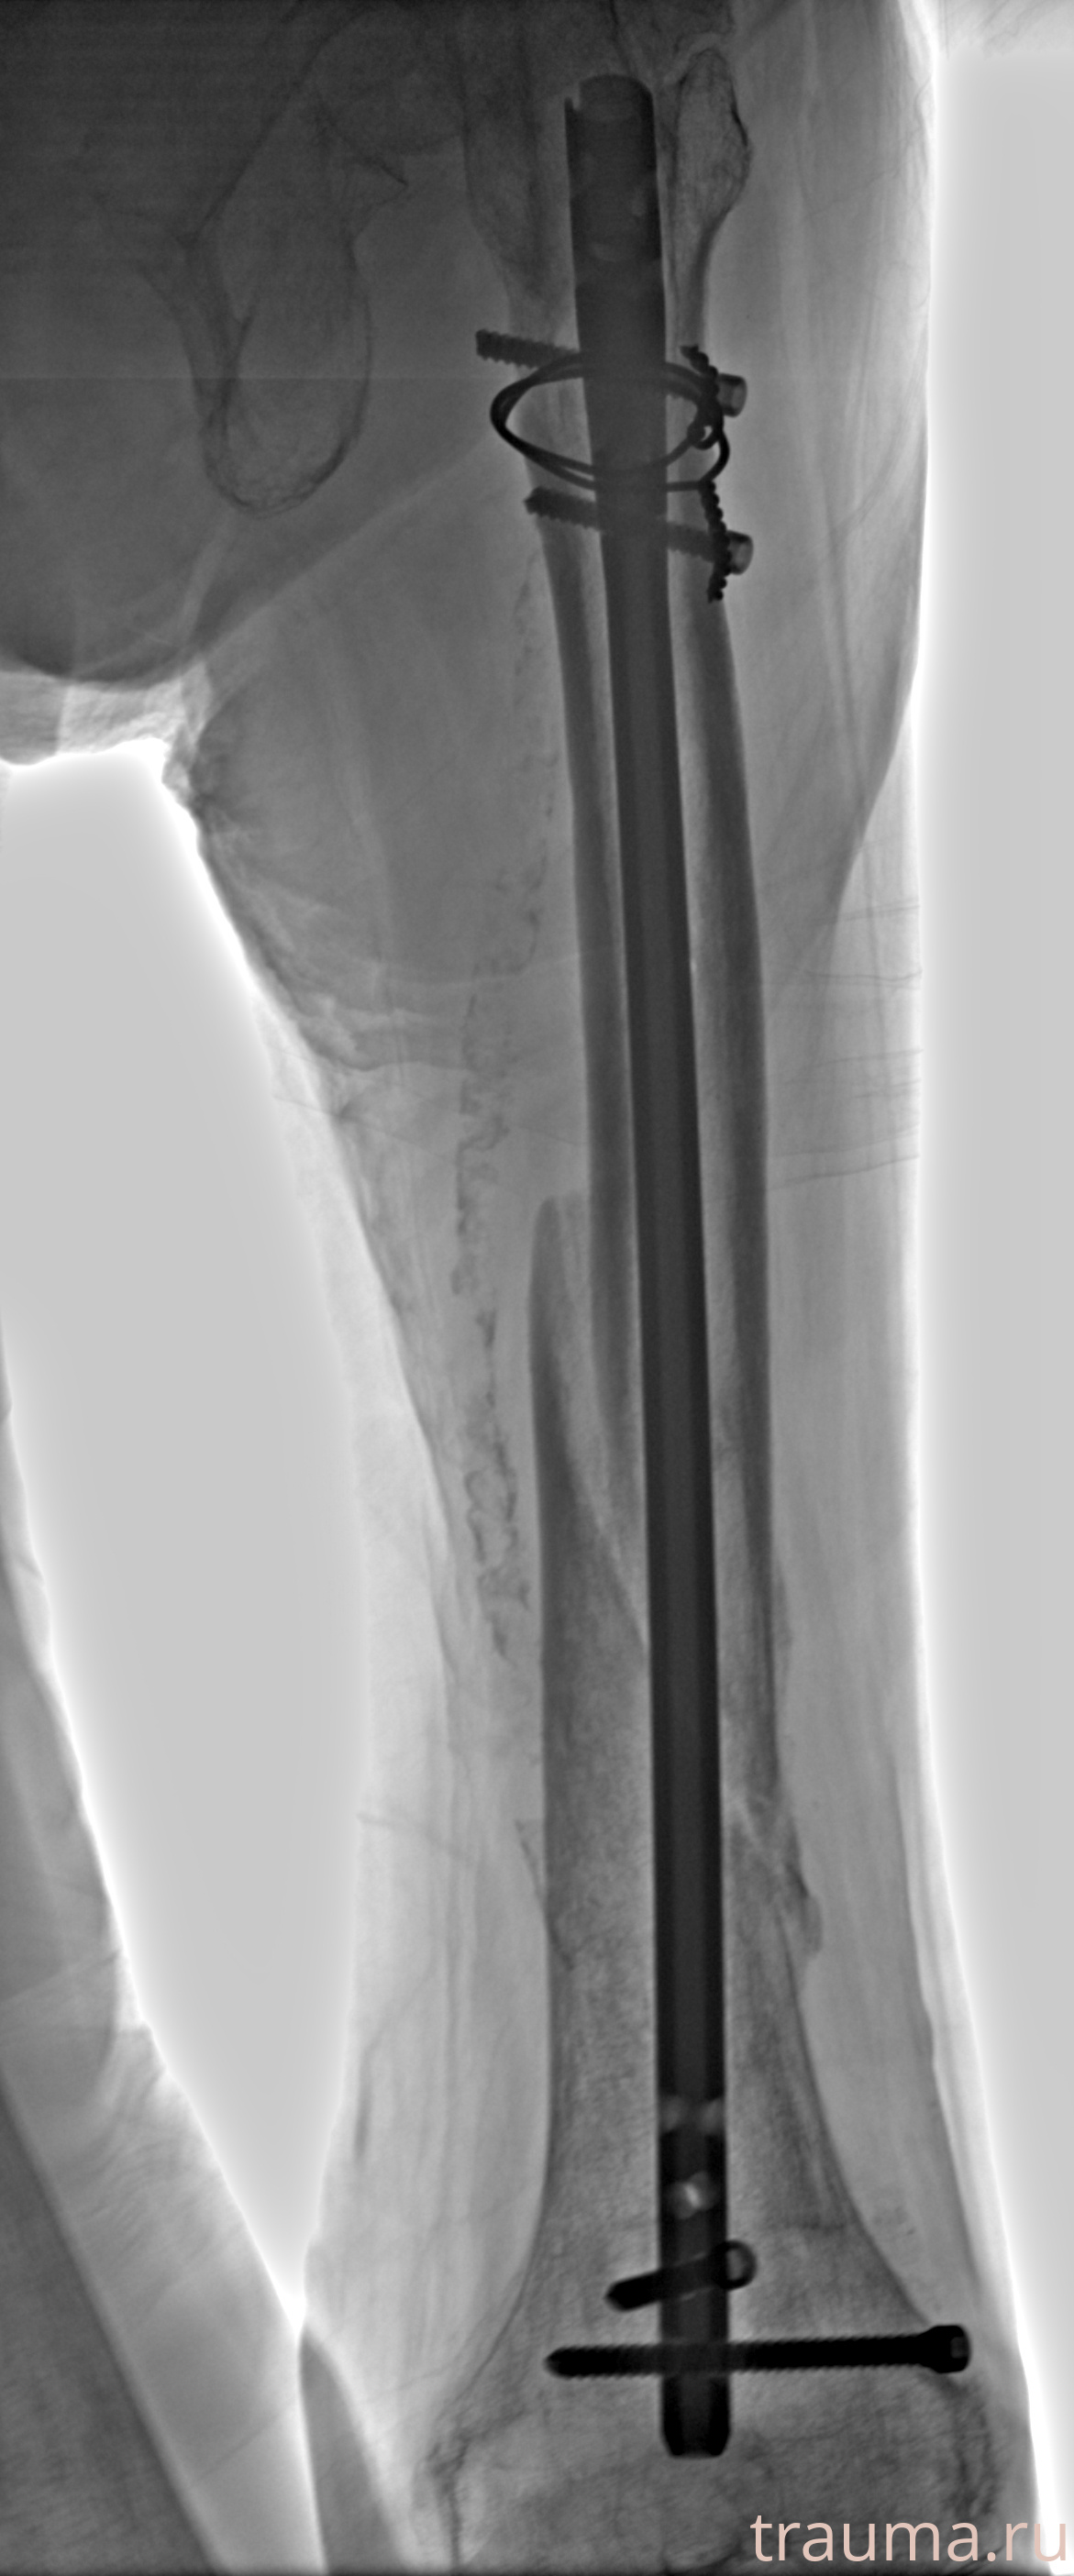

Рентгенограммы

Рентген на дому: по вашему адресу приезжает врач-рентгенолог, травматолог-ортопед с мобильным рентгеновским аппаратом, проводит диагностику травмы или заболевания, делает необходимые рентгенограммы, дает рекомендации по дальнейшему лечению. Получить качественные снимки в домашних условиях возможно благодаря уникальной методике, разработанной МосРентген Центром для института  Склифосовского